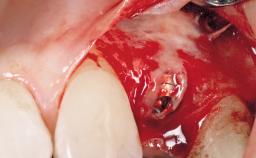

| Bone Augmentation | Horizontal|Simultaneous |

| Augmentation Materials | Xenogenous|Membrane |

| Soft Tissue Grafting | Simultaneous |